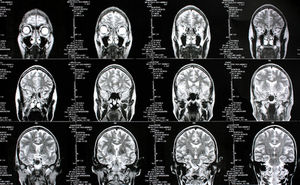

Gehirne: Schizophrenie hat viele Gesichter (Foto: pixelio.de, Rike) |

Granada/St. Louis (pte011/01.02.2016/10:30) Einen Zusammenhang zwischen den Symptomen einer Schizophrenie und den anatomischen Charakteristiken des Gehirns haben Wissenschaftler der Universidad de Granada http://www.ugr.es , der Washington University http://wustl.edu und der University of South Florida http://usf.edu mittels Magnetresonanztomographie hergestellt.

Durch die Analyse der Anatomie des Gehirns konnten die Forscher das Vorhandensein von klar unterscheidbaren Untergruppen bei Patienten mit Schizophrenie nachweisen, die unter unterschiedlichen Symptomen leiden. Mittels Diffusions-Tensor-Bildgebung wurden 36 gesunde Studienteilnehmer und 47 Patienten mit Schizophrenie untersucht.

Die Ergebnisse bei den Personen mit Schizophrenie zeigen, dass sie über verschiedene Anomalien in bestimmten Bereichen des Corpus Callosum verfügen. Dieses Bündel aus Nervenfasern verbindet die rechte und die linke Gehirnhälfte und wird für die Kommunikation zwischen diesen beiden Bereichen als entscheidend angesehen.

Als die Experten Anomalien im gesamten Corpus Callosum entdeckten, stellte sich heraus, dass bestimmte charakteristische Merkmale der Gehirn-Scans mit bestimmten Symptomen der Krankheit übereinstimmten. Patienten mit spezifischen Merkmalen in einem Bereich des Corpus Callosum wiesen zum Beispiel ein eigenartiges und unorganisiertes Verhalten auf. Bei anderen Teilnehmern entsprachen die gefundenen Anomalien spezifischen Symptomen.